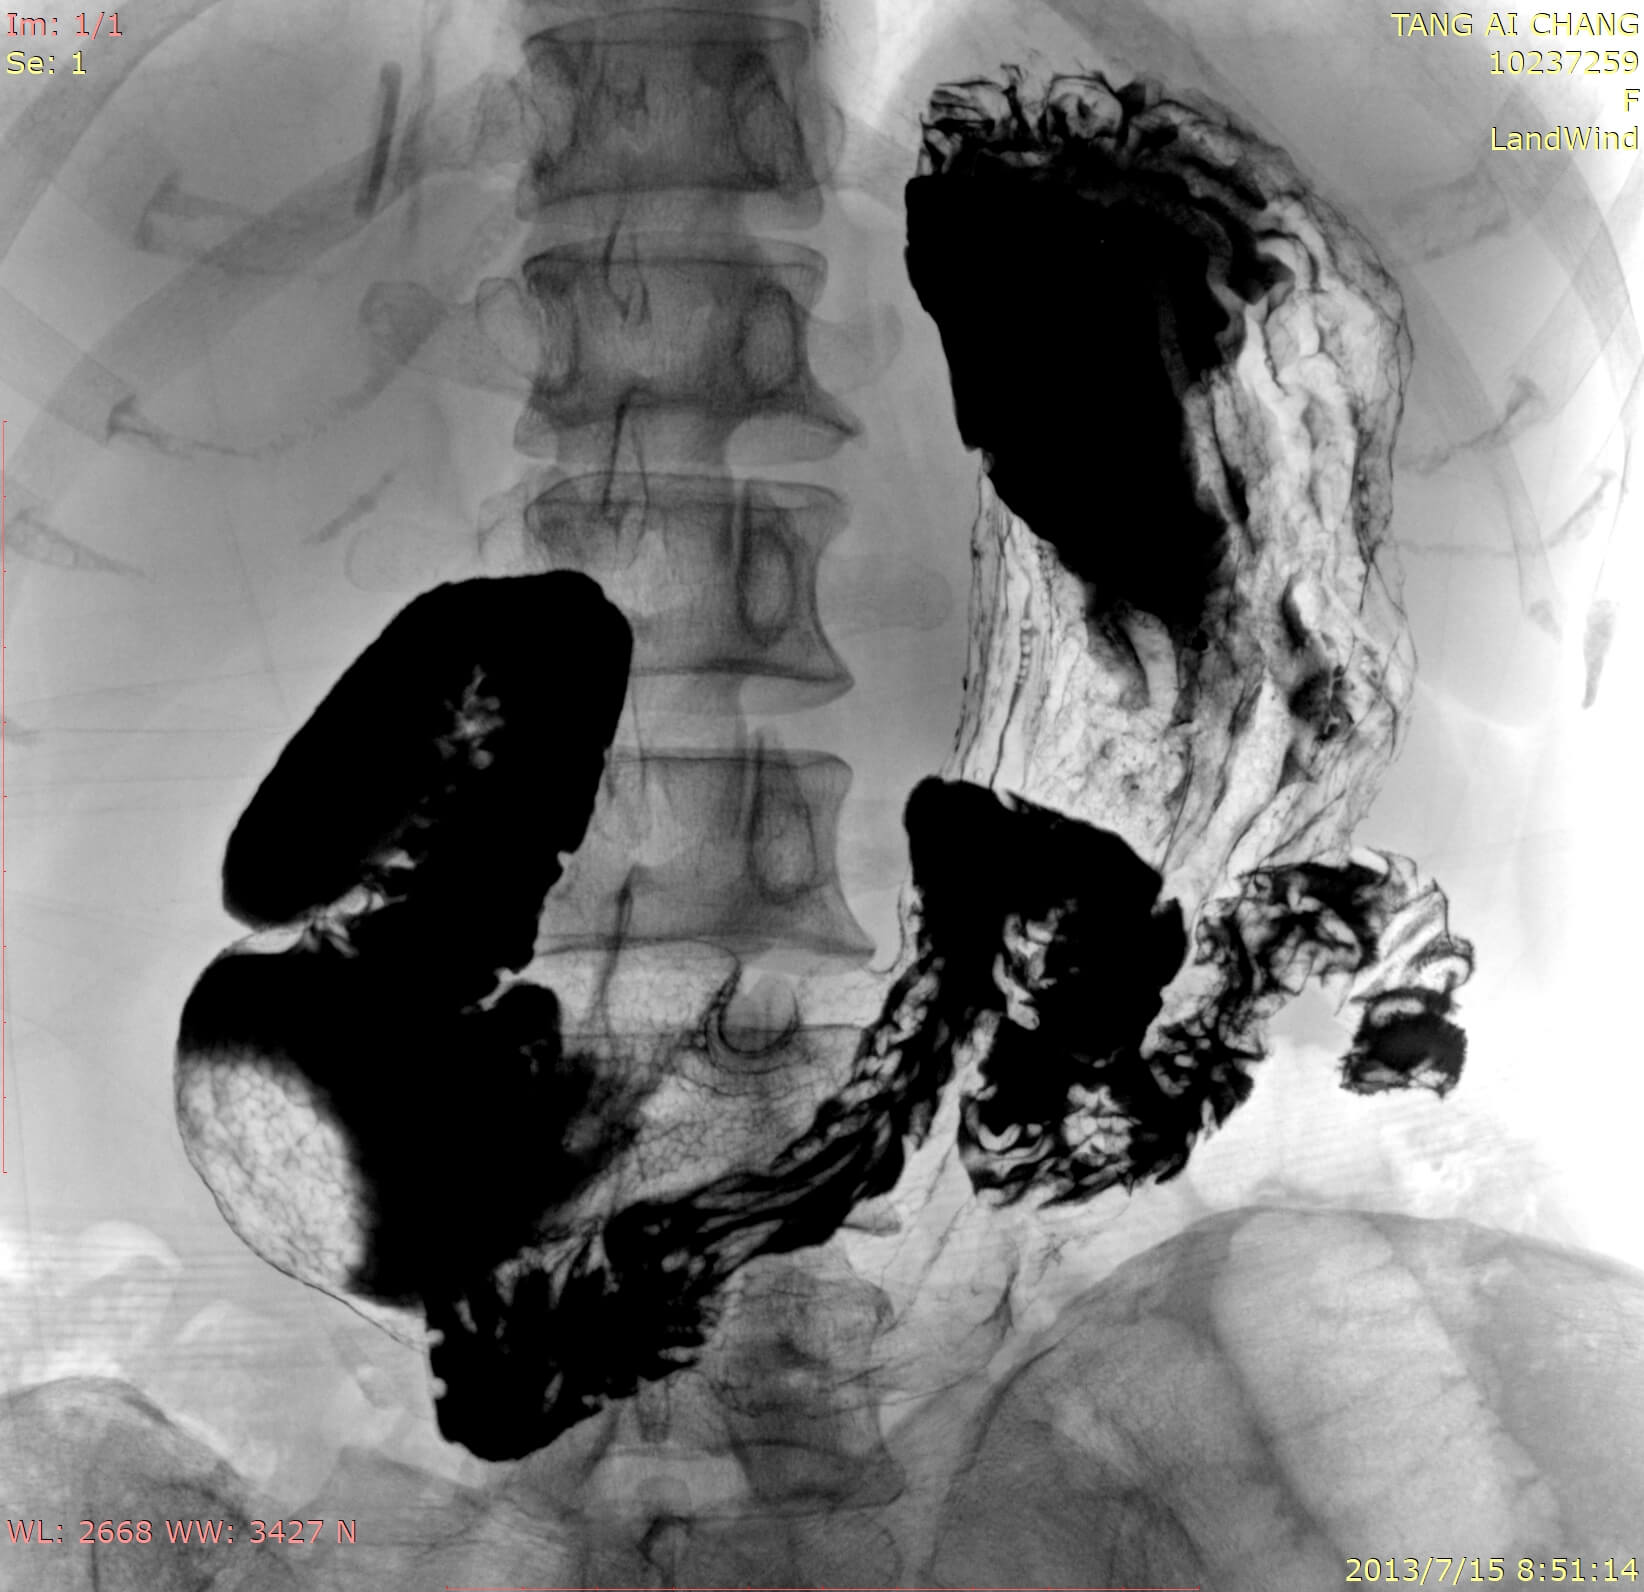

• Combination of Fluoroscopy and Radiography technology

• Wide clinic applications

• Advanced Flat Panel technology-Amorphous Silicon

• Clever post processing of fluoroscopic image